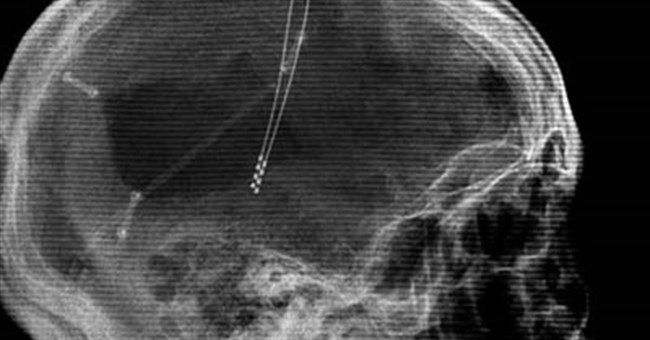

• Đánh thức người sống thực vật

Đánh thức người sống thực vật